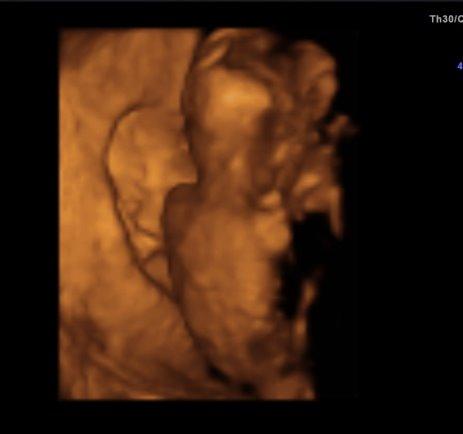

Hallihallo, war ja heute zur VU und wollte euch noch berichten. Soweit ist alles in Ordnung, nur das ich abgenommen habe hat meiner Ärztin nicht gefallen. Ist doch nur 1 kg Baby wiegt 170 g, die Gesamtlänge weiß ich leider nicht genau, laut FÄ richtet man sich da jetzt nach der SSW, also 17cm. Sie hat alles einzeln gemessen, Kopfdurchmesser, Oberschenkel und Bauchdurchmesser und dies entspricht 16+5, ich bin 16+4. Urin okay, Blutruck auch. Zum Geschlecht hat sie sich nicht 100%ig geäußert, da lag die Nabelschnur ungünstig. Schade, schade, aber einen kleinen Verdacht gab es schon, na mal sehen ob sich dieser bei der nächsten VU am 2.11. bestätigt Nun sind es wieder 4 lange Wochen bis dahin Einige Bilder gab es auch, die sind aber diesmal nicht so schön, da das kleine uns den Rücken zugedreht hatte. Naja, ein schöner Rücken kann auch entzücken Das von meiner Seite, hier noch ein Bild.

Bild zu VU Bericht - Forum für März - Mamis

Huhu, schön, dass alles ok ist. Und das Bild finde ich sehr süß, sieht so klein und zerbrechlich aus und schon wie ein richtiges Menschlein LG, Jette